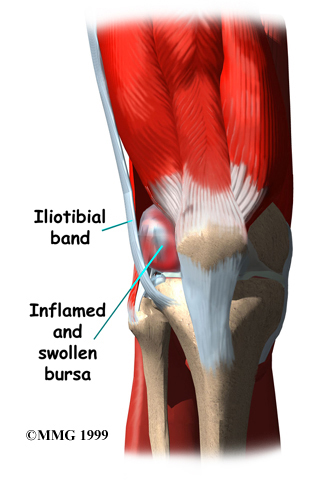

The ITB glides back and forth over the lateral femoral condyle as the knee bends and straightens. Normally, this isn't a problem. But the bursa between the lateral femoral condyle and the ITB can become if the ITB starts to snap over the condyle with repeated knee motions such as those from walking, running, or biking.

People often end up with ITB syndrome from overdoing their activity. They try to push themselves too far, too fast, and they end up running, walking, or biking more than their body can handle. The repeated strain causes the bursa on the side of the knee to become inflamed.

The commonly begin with pain over the outside of the knee, just above the knee joint. Tenderness in this area is usually worse after activity. As the bursitis grows worse, pain may radiate up the side of the thigh and down the side of the leg. Patients sometimes report a snapping or popping sensation on the outside of the knee.

Surgery is rarely needed to correct ITB problems. Surgery consists of removing the bursa and releasing, or lengthening, the ITB just enough so that the friction is reduced when the knee is bent and straightened.